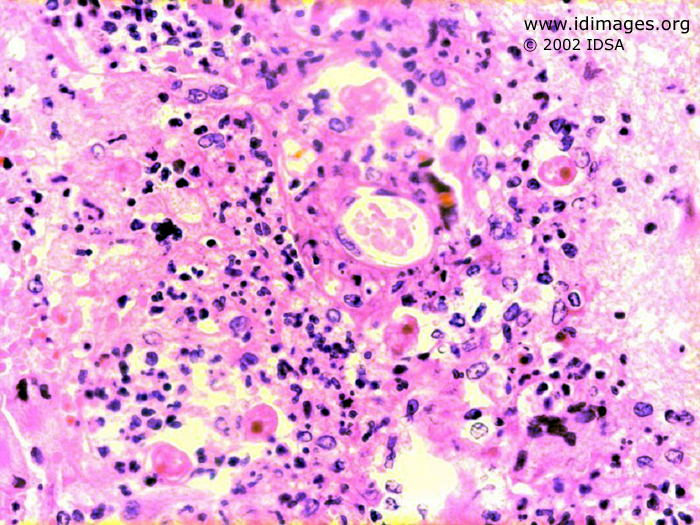

Image from atlas entry: Acanthamoeba castellanii

Figure 1. Acanthamoeba castellanii on hematoxylin and eosin stain of brain biopsy.

Figure 1 contributed by Jyoti Somani, MD, and Frederick Nolte, MD, Emory University, Atlanta, GA. Copyright 40th Annual Meeting of Infectious Disease Society of America (IDSA), 2002. Used with permission. Please refer to the Contributors page for the list of IDSA 2002 Contributors.